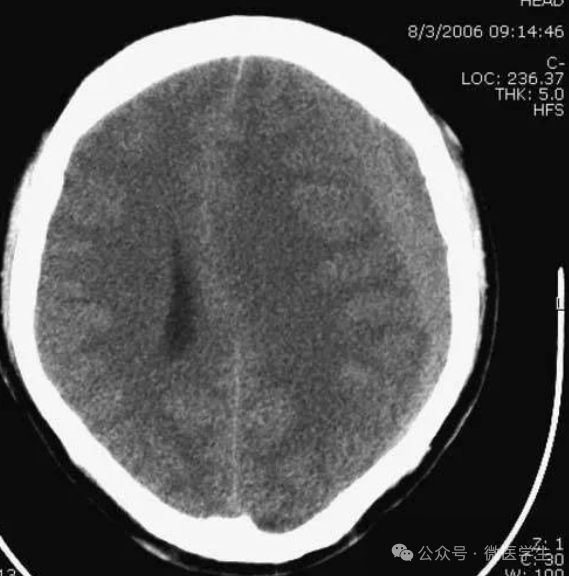

左侧硬膜下血肿:

呈等密度,有占位效应,中线结构移位。

▲

双侧亚急性硬膜下血肿:

左侧可见急性出血,双侧占位效应平衡,

中线结构无移位